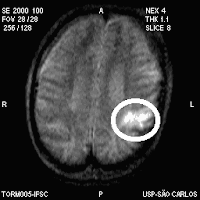

Caso Clínico (Tratamento)